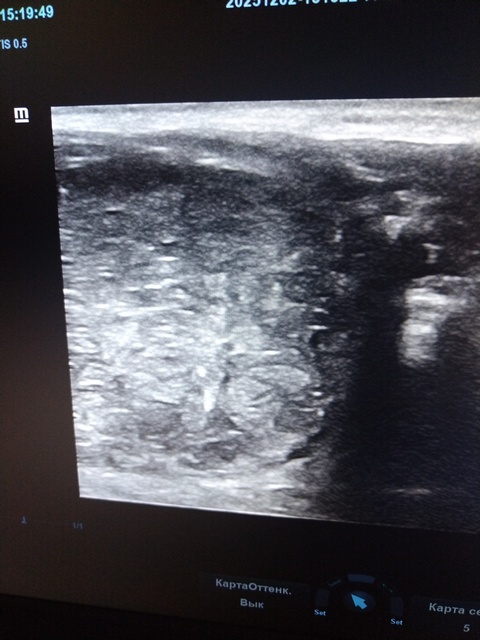

Ветеринарными специалистами ГБУ Брянской области «Унечская райветстанция» была проведена кастрация кобеля породы йоркширский терьер, которому был поставлен диагноз - крипторхизм. Животному 5 лет, правый семенник не опустился в мошонку, а остался в паховом канале. При пальпации отмечалась болезненная реакция животного. Дополнительно было проведено ультразвуковое исследование. Обнаружено перерождение паренхимы семенника и развитие неопластического процесса. Это и стало показанием для оперативного вмешательства.